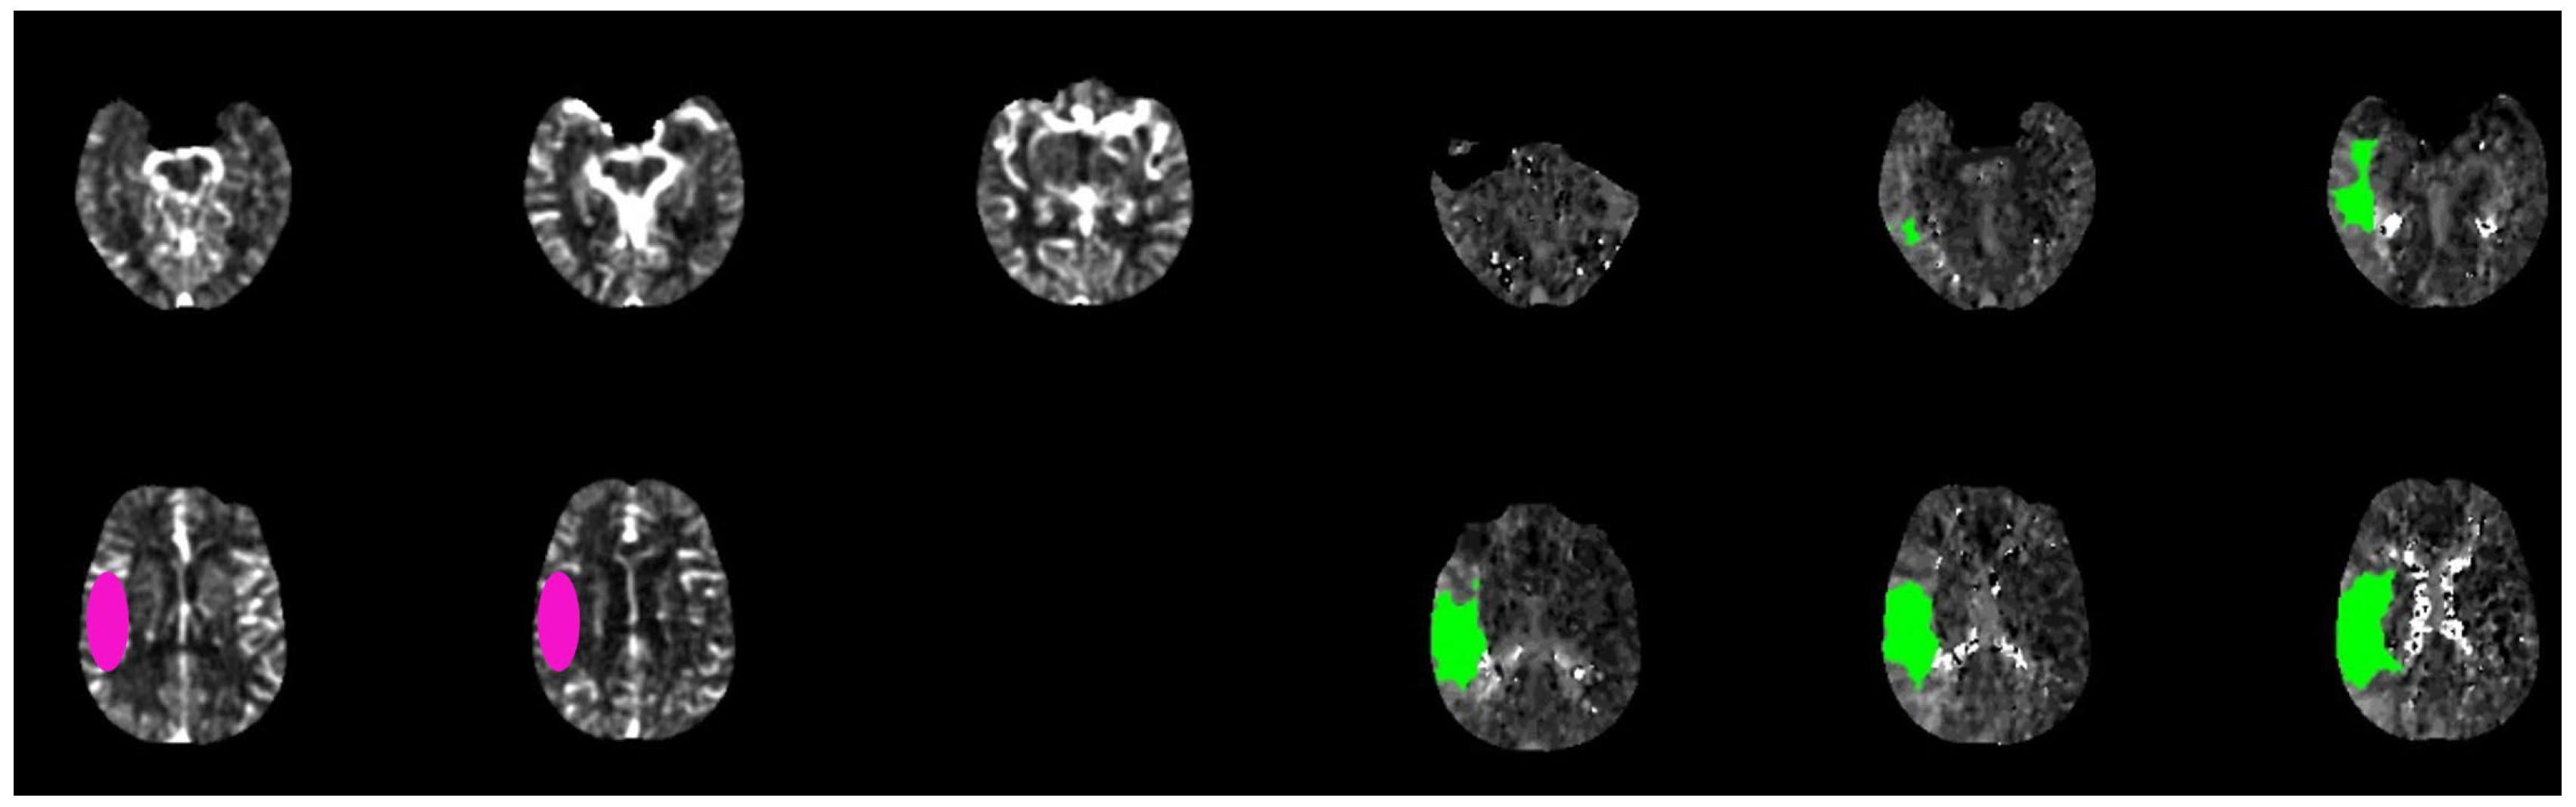

3.2. Automatic Assessment